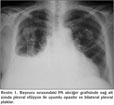

Yetmi? iki ya??nda, hipertansiyon ve atriyal fibrilasyon tan?lar?yla takip edilen hasta bir hafta ?nce ba?layan nefes darl???, ?ks?r?k ve sa? yan a?r?s? yak?nmalar?yla ba?vurdu. Ek hastal?k ve travma ?yk?s? bulunmayan hastan?n ?z ge?mi?inde ?evresel asbest maruziyeti mevcuttu. Fizik muayenede arteryel kan bas?nc? 100/60 mmHg ve nab?z 97/dakika-aritmikti. Sa? hemitoraksta skapula alt?nda solunum sesleri, vibrasyon torasikte azalma ve perk?syonda matite saptand?. Arter kan gaz? analizinde PaO2: 65 mmHg, PaCO2: 34 mmHg, pH: 7.46 ve SaO2: %95 idi. Laboratuvar incelemesinde Hb: 14.7 g/dL, Htc: %44.3, trombosit: 456 x 103/dL, l?kosit: 8.5 x 103/dL, eritrosit sedimentasyon h?z? 60 mm/saat idi. Kan biyokimyas? ve idrar analizi normaldi. Atriyal fibrilasyon nedeniyle warfarin tedavisi alan hastada PT: 111.5 saniye (N: 9.4-12.5 saniye) ve INR de?eri 8.85 (N: 0.82-1.07) olarak bulundu. G???s radyografisinde sa? alt zonda plevral ef?zyon ile uyumlu opasite ve d?zensiz s?n?rl? plevral plaklar izlendi (Resim 1). Ba?ka bir merkezde ?ekilen toraks bilgisayarl? tomografi anjiyografide tromboemboli ile uyumlu bulgu yoktu ve sa? akci?erde en kal?n yerinde 8 cm ?l??len plevral ef?zyon ve kom?ulu?unda subsegmenter atelektazi ve her iki akci?er ?st lob ve alt lob plevras?nda en kal?n yerinde 15 mm olan d?zensiz plevral kal?nla?ma ve kalsifik plaklar izlendi (Resim 2). Warfarin tedavisi kesilerek K vitamin replasman? yap?ld?. Normal INR d?zeyi sa?lanan hastaya tan?sal torasentez yap?ld? ve yakla??k 40 cc defibrine hemorajik s?v? aspire edildi. Plevral s?v? k?lt?r?nde ?reme olmad?. Sitolojik incelemede periferik kan elemanlar? aras?nda histiyosit ve reaktif mezotel h?creleri izlenen olguda, plevral s?v? hematokriti kan hematokritinin %50'sinden b?y?k saptanmas? ?zerine hemotoraks tan?s? konuldu. Hemotoraks miktar?n?n az olmas?, p?ht?l? olmamas? ve spontan olarak geriledi?inin izlenmesi nedeniyle drenaj yap?lmad?. Takiplerinde radyolojik d?zelme izlenen hasta komplikasyonsuz taburcu edildi (Resim 3).

Resim 3

Hemotoraksl? olgularda uygulanan temel tedavi, kanl? s?v?y? bo?altmak ve devam eden kanaman?n yo?unlu?unu belirlemek amac?yla g???s t?p? tak?larak drenaj uygulanmas?d?r. Bizim olgumuzda ise hemotoraks miktar?n?n az olmas?, p?ht?l? olmamas? ve spontan olarak geriledi?inin izlenmesi nedeniyle drenaj yap?lmad?. Warfarin tedavisi kesilerek uluslararas? k?lavuz temel al?narak oral K vitamini uyguland? ve yat???n?n ikinci g?n?nde hastada normal INR d?zeyine ula??ld? (16).